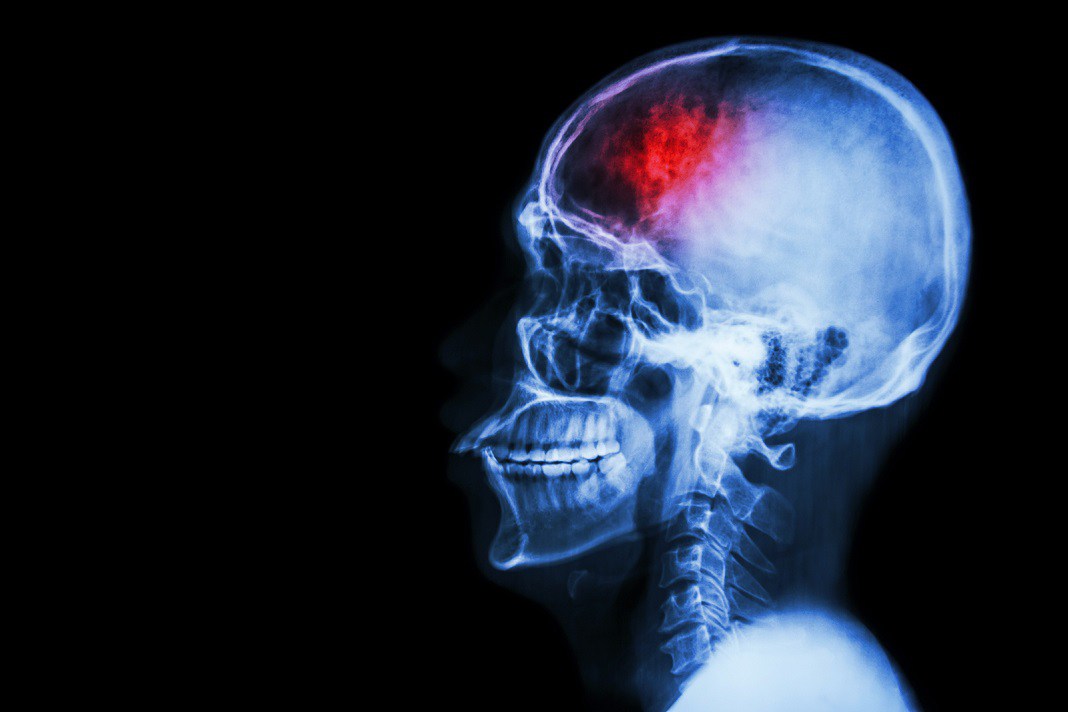

Learn about the causes of a stroke in the video from CHI Health below: